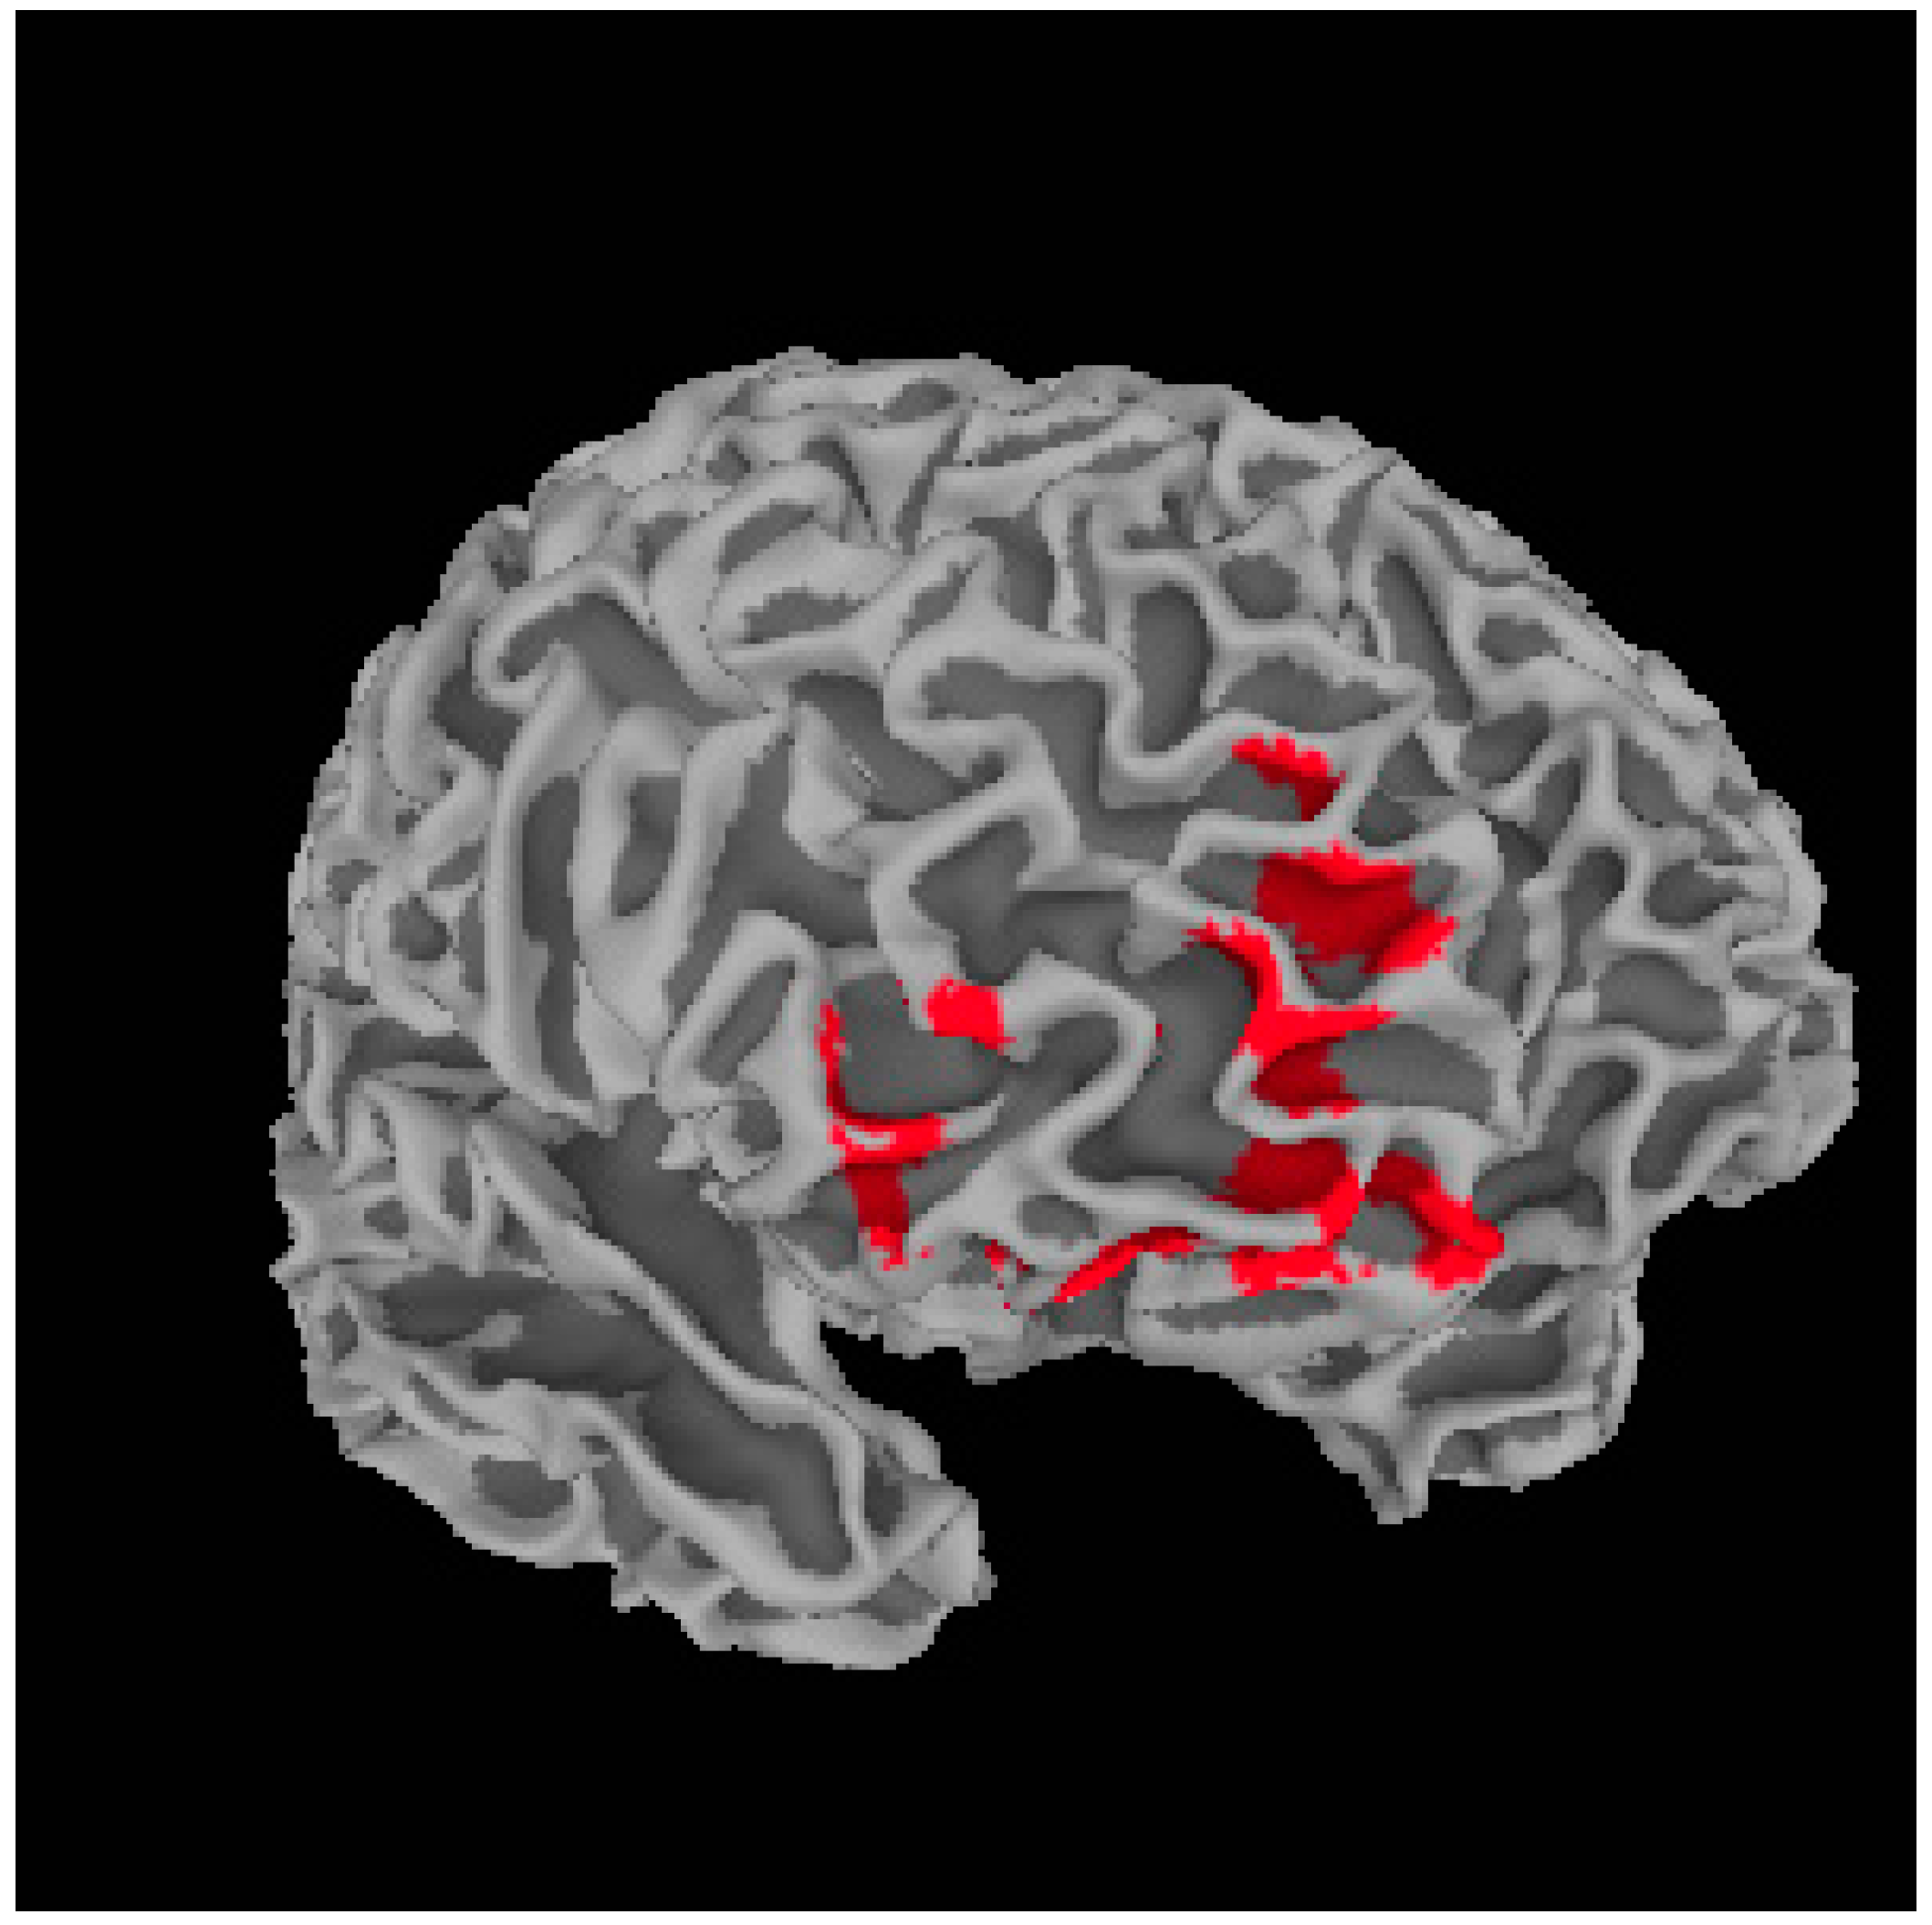

Metacognition and Whole Brain Gray Matter Density

| Region | R/L | BA | MNI Coordinates (x, y, z) | t-Value (Peak Voxel) | Cluster Size (Voxels) |

|---|---|---|---|---|---|

| Dorsal Lateral Prefrontal Cortex | L | 10 | −32, 47, 7 | 6.22 | 692 |

| Dorsal Lateral Prefrontal Cortex | R | 10/11 | 27, 34, 24 | 6.00 | 589 |

| Medial Prefrontal Cortex | R | 10/11 | 18, 62, 7 | 5.75 | 1684 |

| Ventral Striatum | R | – | 10, 16, −6 | 4.77 | 611 |

| Precentral Gyrus | R | 4 | 63, −1, 45 | 4.44 | 747 |

| Anterior Cingulate Cortex | L | 32 | −3, 36, 27 | 4.39 | 860 |

| Region | MAS-A | Self-Reflect | Other-Reflect | Mastery |

|---|---|---|---|---|

| L.DLPFC | 0.455 * | 0.472 * | 0.274 | 0.522 ** |

| R.DLPFC | 0.650 ** | 0.686 ** | 0.462 * | 0.640 ** |

| mPFC | 0.565 ** | 0.606 ** | 0.411 * | 0.572 ** |

| VS | 0.506 ** | 0.405 * | 0.420 * | 0.524 ** |

| Precentral Gyrus | 0.260 | 0.275 | 0.087 | 0.312 |

| ACC | 0.568 ** | 0.599 ** | 0.455 * | 0.563 ** |

| Region | R/L | BA | MNI Coordinates (x, y, z) | t-Value (Peak Voxel) | Cluster Size (Voxels) |

|---|---|---|---|---|---|

| Medial prefrontal cortex | R | 9/10 | 18, 63, 7 | 4.07 | 2482 |

| Region | MAS-A | Self-Reflect | Other-Reflect | Mastery |

|---|---|---|---|---|

| mPFC | 0.566 ** | 0.605 ** | 0.424 * | 0.564 ** |

| VS | 0.464 * | 0.451 * | 0.367 | 0.513 ** |